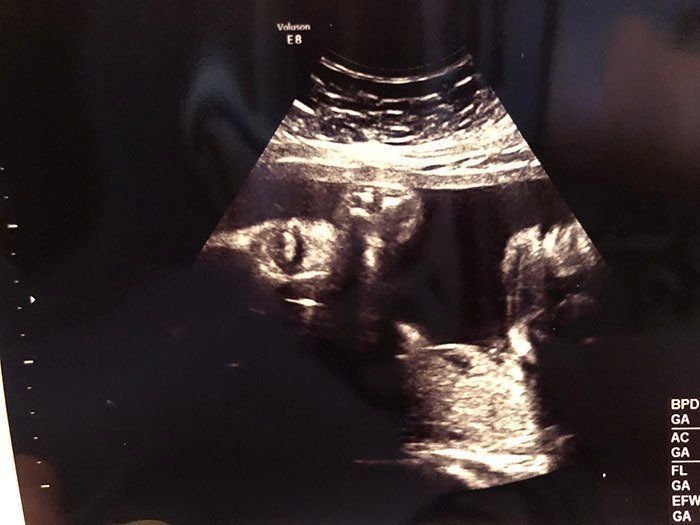

妊娠21週目 つわりからの解放、食欲が少しずつ戻る

妊娠21週目のエコー写真です。すでにつわりが落ち着き、食欲も出てきた頃で、マタニティマークをつけていなくてもバスの席を譲ってもらえるほど、おなかが目立ってきていました。そのせいもあるのか、この時期は腰痛になってしまい、骨盤ベルトを常に締めて過ごしていました。